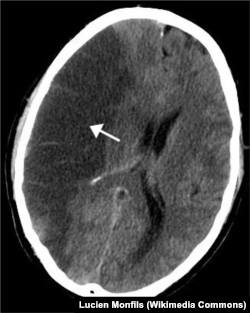

Изображение поврежденного участка мозга, полученное методом компьютерной томографии

На сегодняшний день клиническая диагностика инсульта производится с помощью компьютерной томографии (КТ), которая определяет, произошло ли кровоизлияние в мозг. Стефен Меарис из университета Мангейма считает, что перспективным способом диагностики является магнитно-резонансная томография (МРТ) – более чувствительный по сравнению с КТ метод, требующий, однако, больше времени для проведения. МРТ позволяет получить более контрастное изображение с более четкой различимостью белого и серого вещества, лучшим качеством изображения базальных, стволовых, корковых структур по сравнению с КТ. Впрочем, МРТ и КТ могут применяться как взаимодополняющие методы диагностики.